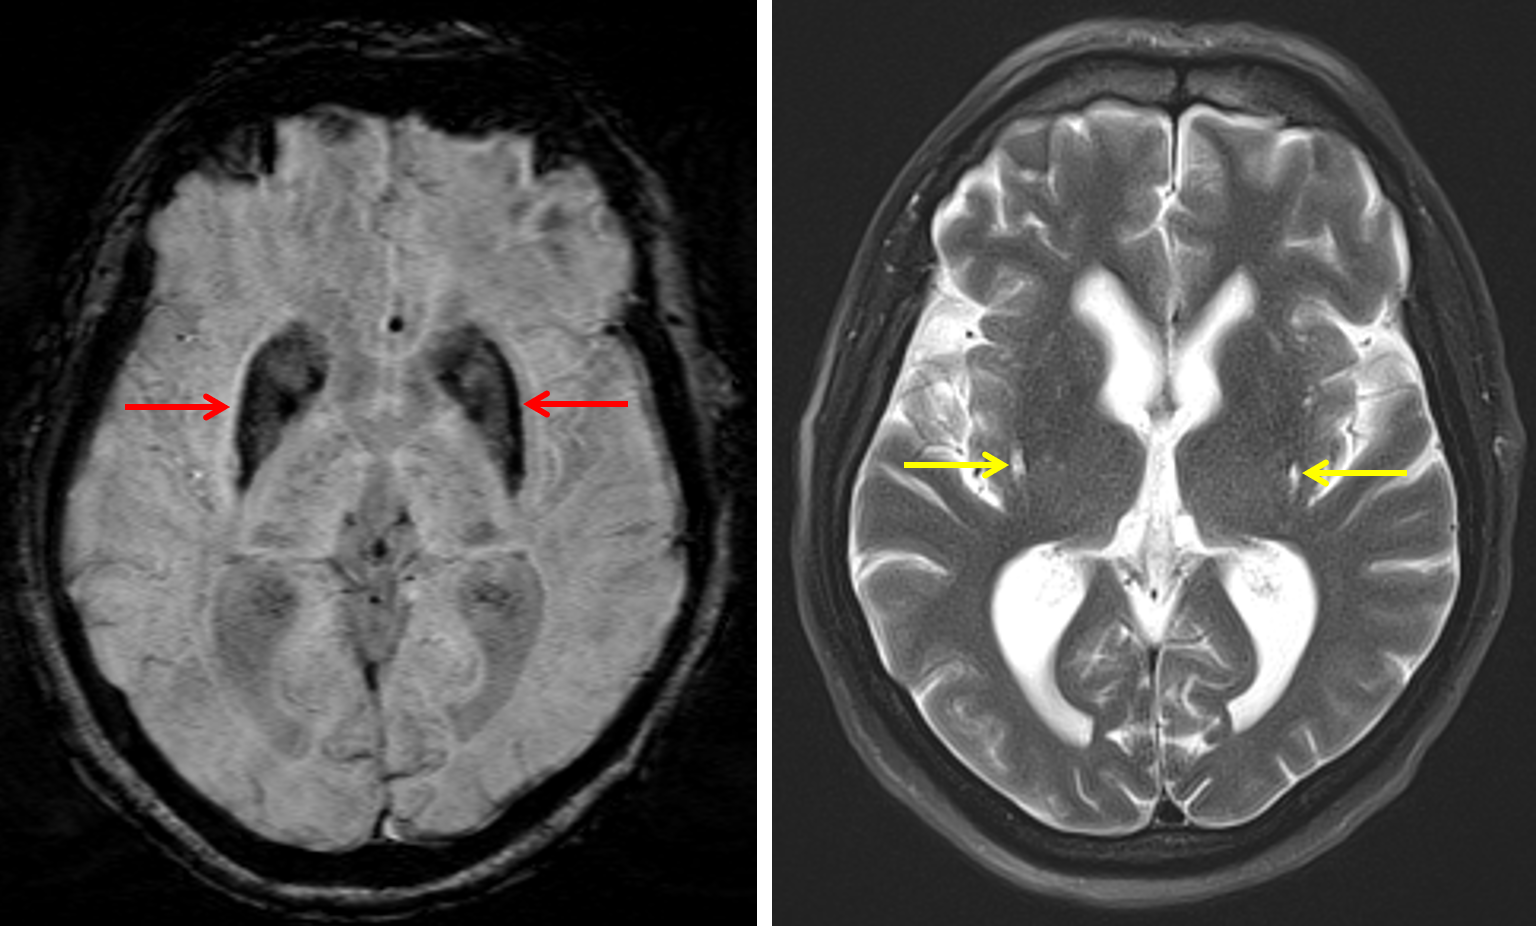

Parkinson-type multiple system atrophy (MSA-P)

Greater than expected susceptibility artifact involving the basal ganglia (particularly the lateral putamina), substantia nigra, red nuclei, and dentate nuclei with linear T2/FLAIR signal hyperintensity along the lateral putaminal margins/subinsular regions which can be seen with Parkinson-type multiple system atrophy (MSA-P) or neurodegeneration with brain iron accumulation (NBIA).